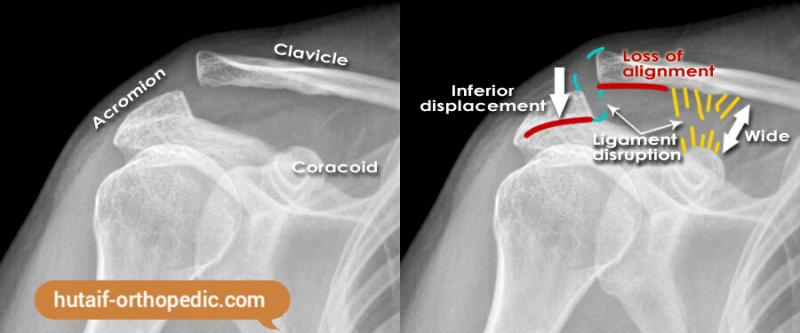

Imaging

Radiographs

AP, scapular Y (45° from coronal plane) and axillary (shoulder abducted 70° and beam shot through the axilla) views of the shoulder should be obtained

- Axillary view can visualize anterioposterior displacement

- Comparison with the contralateral shoulder is helpful

Type II: AC ligaments disrupted, CC ligaments intact

- AC joint may be widened (> 6 mm)

Type III: AC and CC ligaments disrupted

- Widened AC and CC intervals

Type VI: inferior displacement of distal clavicle under coracoid